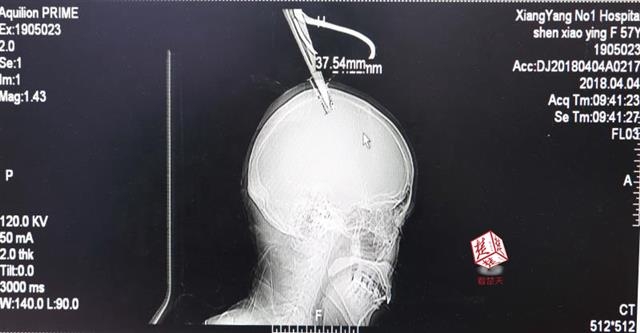

4月4日清晨,襄陽市樊城區(qū)太平店鎮(zhèn)57歲的農(nóng)村婦女沈某,在采摘香椿嫩芽時,綁在竹桿上的剪刀因竹子腐朽不慎折斷,剪刀斜插入頭顱。經(jīng)過及時搶救,目前脫離生命危險。

醫(yī)生檢查發(fā)現(xiàn),剪刀刀尖斜嵌在沈某顱骨里,離腦髓只有兩三毫米。所幸是斜著插進(jìn)去,如果是垂直刺入,很有可能造成癱瘓。最終經(jīng)過手術(shù),剪刀被取出,沈某目前仍在ICU進(jìn)一步觀察。